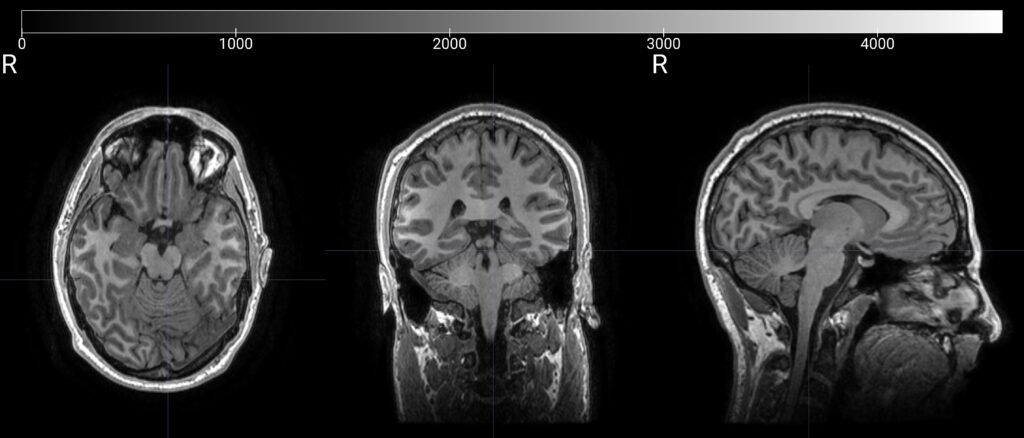

MRI (Magnetic Resonance Imaging)

MRI provides detailed images of brain structure and anatomy.

This allows clinicians to visualize key areas of the brain and better understand the structural context of each patient.

MRI may be used alongside EEG and HALO insights to support a more comprehensive evaluation and treatment planning process.

– High-resolution anatomical imaging

– Supports clinical evaluation

– Provides structural context for care